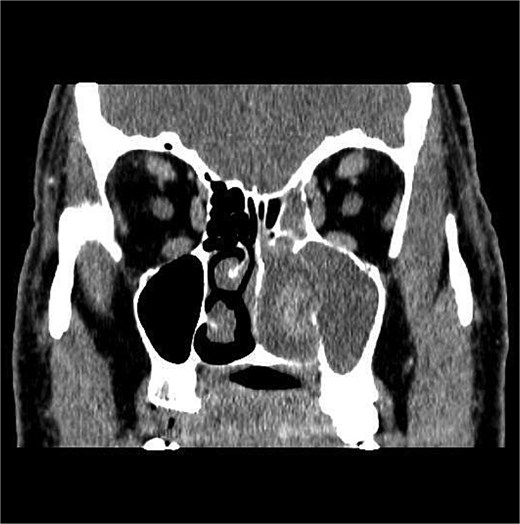

The patient underwent staging CT which was negative for distant metastasis. He then went underwent incomplete medial maxillectomy, ethmoidectomy, and sphenoidotomy followed by 10 sessions of immunotherapy abroad. He presented to our institution for follow up 6 months later with history of left nasal block and epistaxis. Nasal flexible scope showed a reddish nasal mass with greenish secretions (Fig. 3). Follow up CT revealed tumor recurrence (Figs 4 and 5). He was advised for multidisciplinary team evaluation to plan the treatment but he refused any intervention and lost follow up.

Coronal section of CT paranasal sinus bone window showing bony erosions of nasal septum, maxillary wall, lamina papyracea, and cribriform plate.